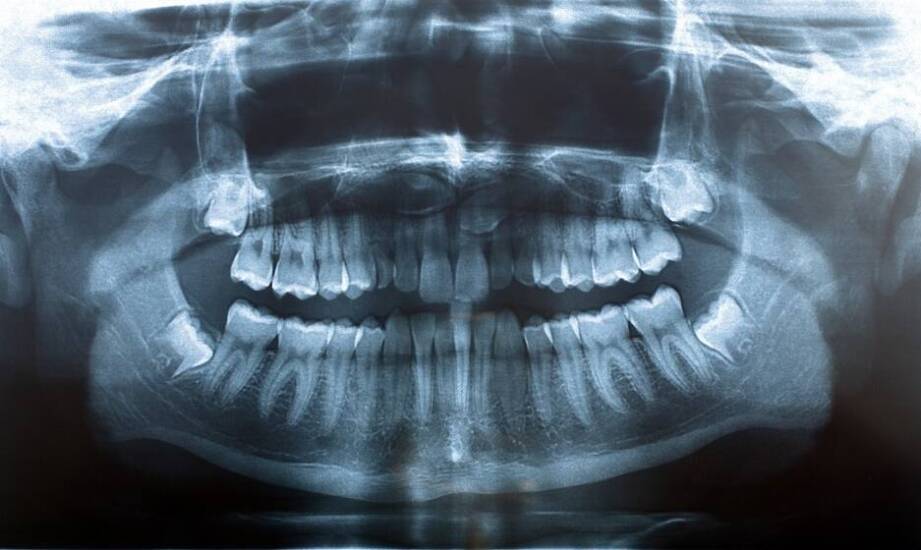

Nowoczesne metody diagnostyczne w ortodoncji obejmują różnorodne techniki, które pozwalają na zrozumienie problemów pacjentów. Tomografia komputerowa oraz skanowanie 3D to przykłady metod umożliwiających określenie rodzaju wady oraz jej wpływu na funkcjonowanie jamy ustnej. Dzięki tym technologiom specjaliści mogą analizować indywidualne potrzeby i dostosować leczenie do wymagań każdego z nich. Ortodoncja we Wrocławiu i innych miastach korzysta z rozwiązań diagnostycznych, co może wspierać planowanie terapii. Regularne wizyty kontrolne oraz monitorowanie postępów są istotne dla oceny przebiegu leczenia i utrzymania zdrowia jamy ustnej.

Wybór odpowiedniego aparatu ortodontycznego jest istotny w planowaniu leczenia. Dzięki diagnostyce lekarze mogą ocenić rodzaj wady i dobrać właściwe rozwiązanie. W zależności od potrzeb pacjentów oraz specyfiki problemu, mogą zalecać aparaty stałe, ruchome lub estetyczne. Technologie, takie jak skanowanie 3D, pozwalają na dokładniejszą analizę i planowanie terapii. Każde z rozwiązań ma swoje cechy; aparaty stałe są stosowane w przypadku bardziej złożonych wad, podczas gdy ruchome mogą być stosowane u dzieci z jeszcze rozwijającym się uzębieniem. Estetyczne opcje, takie jak ceramiczne czy przezroczyste, są mniej widoczne i bywają wybierane przez dorosłych. Ortodoncja we Wrocławiu - cennik oraz dobór aparatu mogą mieć znaczenie dla przebiegu leczenia ortodontycznego.